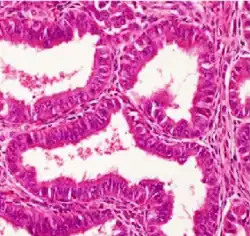

| Histopathology of a well-differentiated endometrioid adenocarcinoma in the ovary | |

Light microscopy shows tubular glands, resembling endometrium.[8]